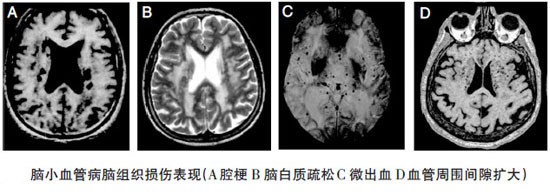

脑白质疏松症影像表现